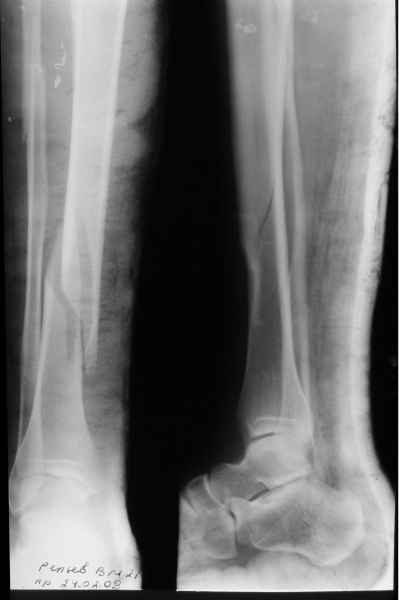

остеосинтеза (кроме детей, разумеется). На прошлой неделе оперировали 11-летнюю девочку с низким переломом обеих костей голени. Гвоздик не поставить и пластинка вроде как перекрывает зону роста. Аппарат пришелся как нельзя кстати.

Ведь у каждого случалось лечить пациентов с переломами месячной и более давности. Так вот одномоментно выправить "ось-длину-ротацию" уместно как раз постепенно. Затем забить гвоздь и все. Ваш аппарат, видимо, будет обладать всеми необходимыми для этого